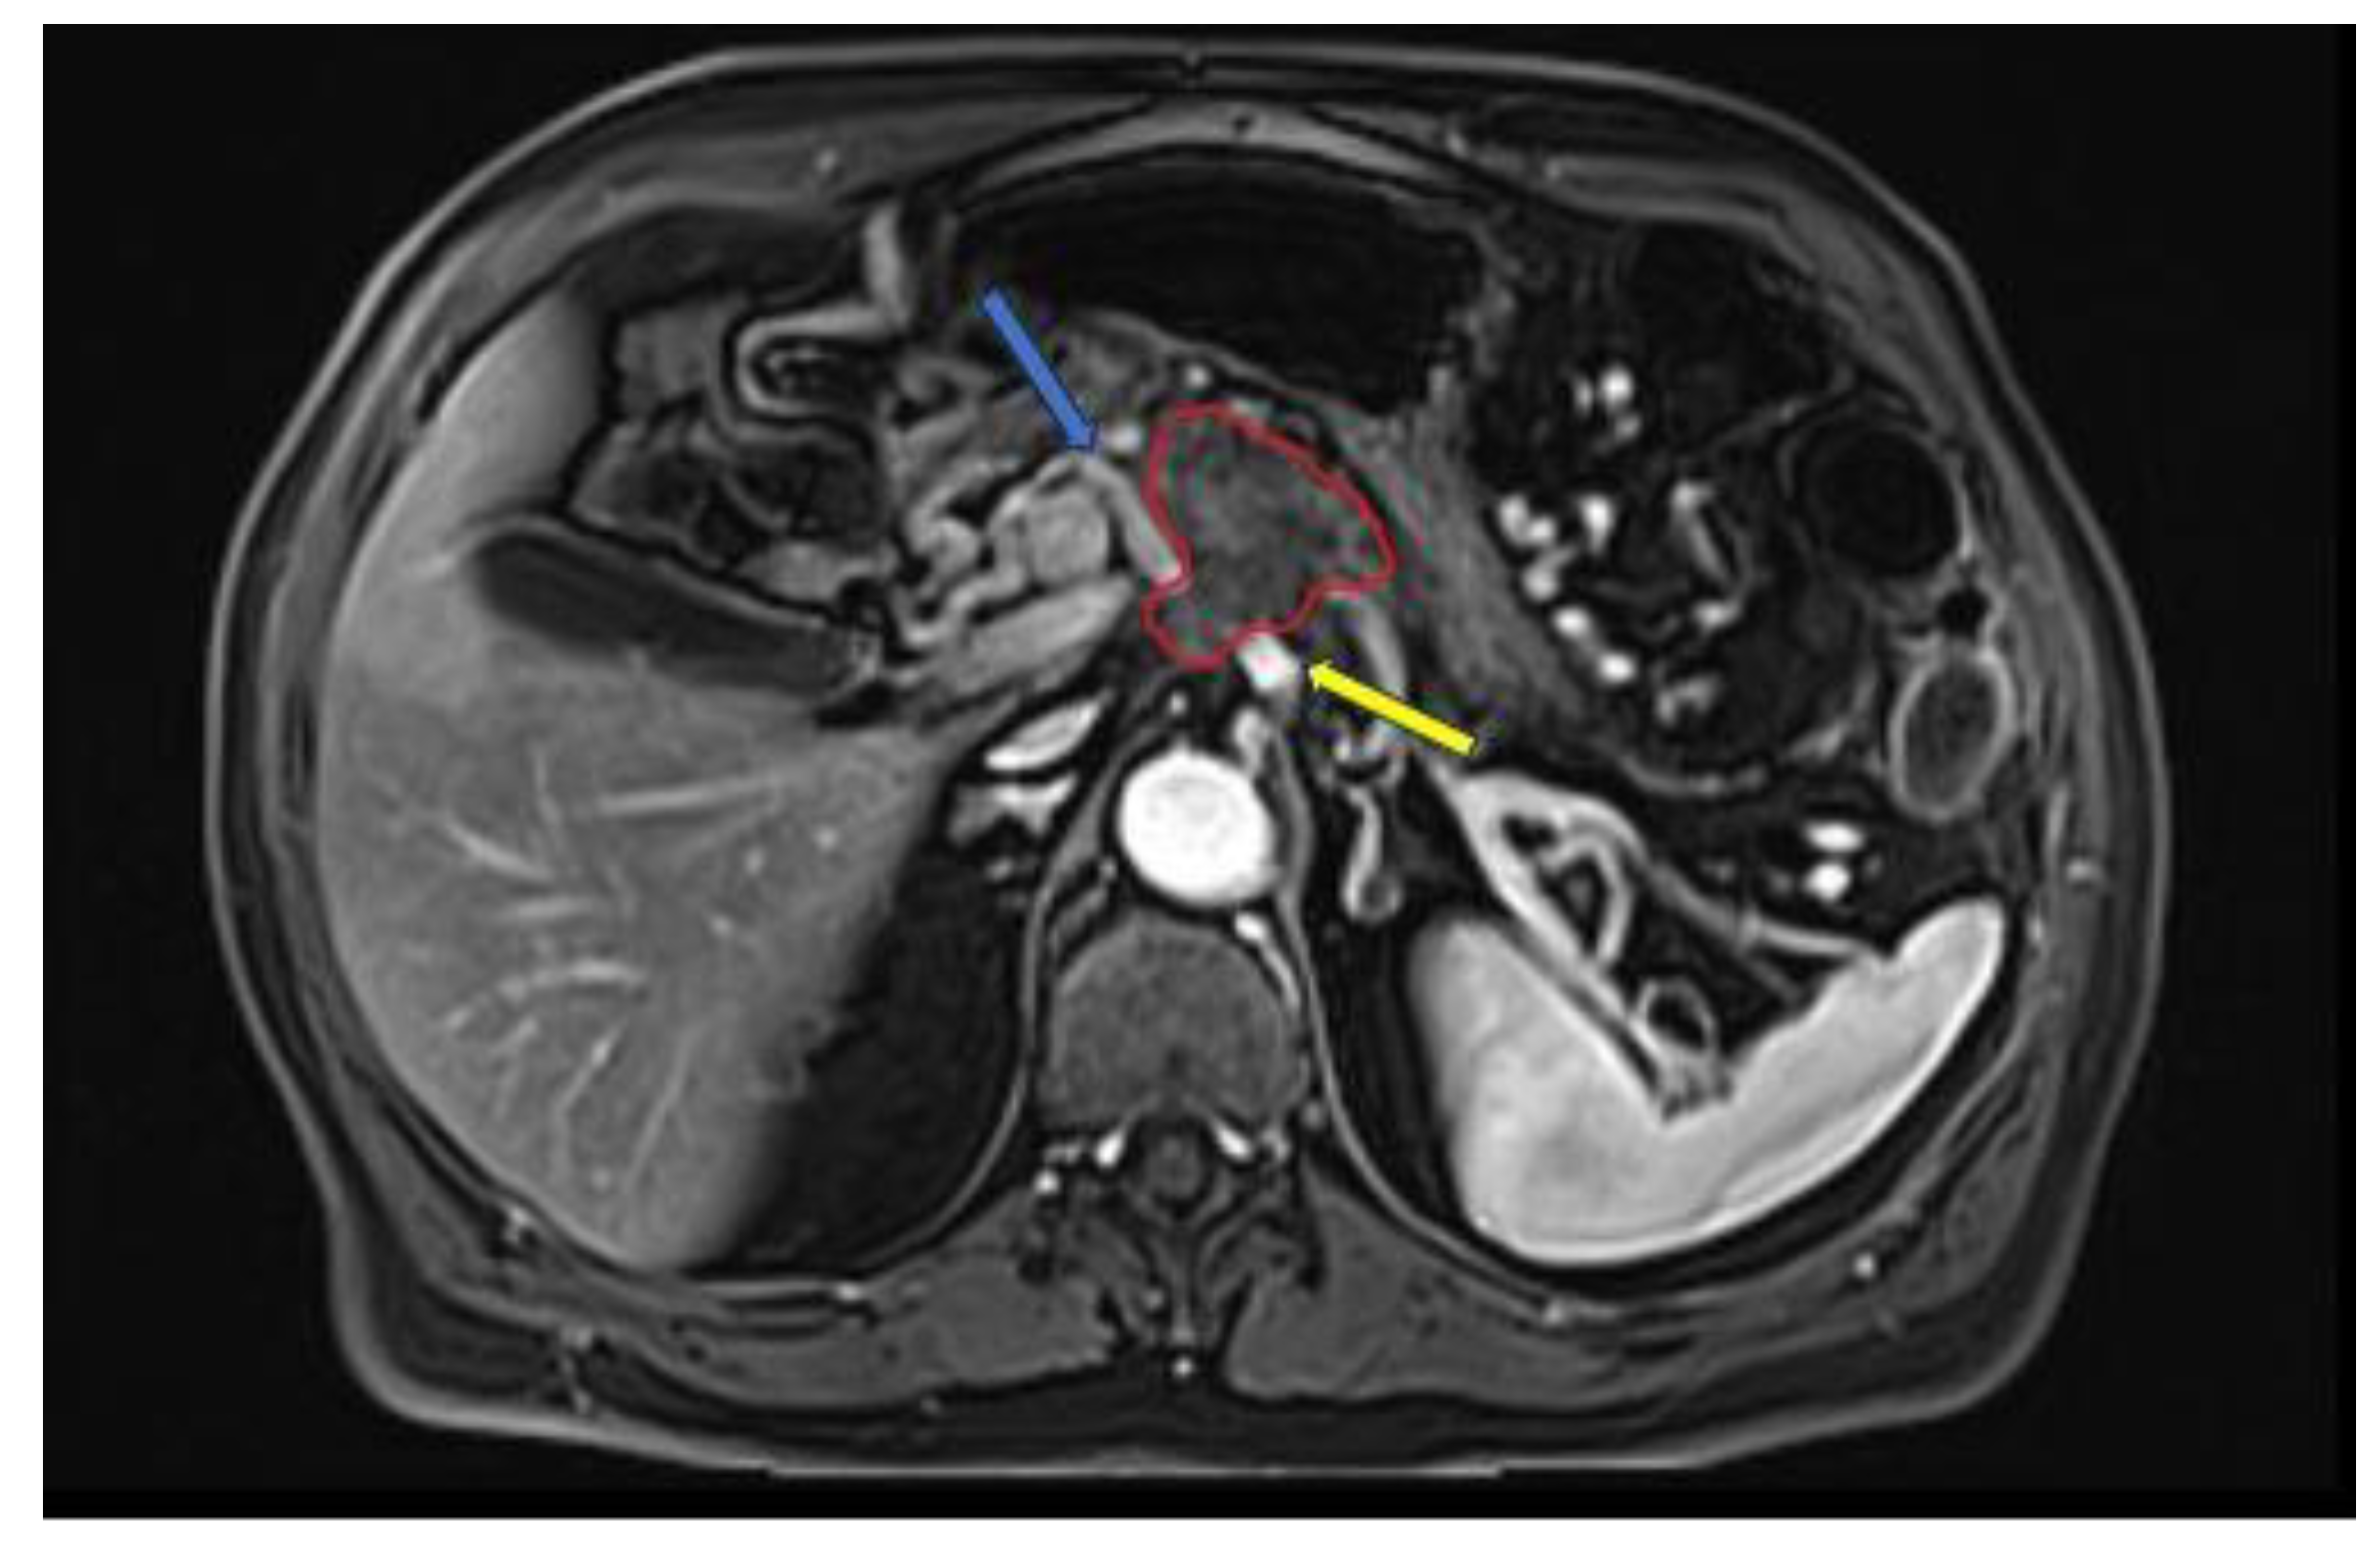

MRI has higher soft tissue contrast resolution, but it is not superior to CT in staging of PDAC [28]. According to some studies, MRI is useful in characterizing smaller and isoattenuating tumors on CT, as well as distinguishing focal fatty infiltration from a tumor [29,30]. The MRI protocol recommended by the NCCN for evaluation of PDAC consists of: T2-weighted imaging (WI) single shot fast spin-echo (SSFSE) in coronal and / or axial; T1WI in-phase and out-phase gradient echo (GRE) in axial plane; T2WI fat-suppressed fast spin-echo (FSE) in axial plane; diffusion weighted imaging (DWI) in axial plane; pre and dynamic post intravenous contrast administration 3D T1WI fat-suppressed GRE in the pancreatic, portal venous and equilibrium phases, in axial plane; and T2WI cholangiopancreatography (MRCP) in coronal plane [24,31]. An example of PDAC diagnosed at MRI is shown in Figure 3. A study by Fang-Ming Chen et al. that compared CT and MRI in the presurgical evaluation of pancreatic cancer on 38 patients showed that the evaluation of vessel involvement, nodal status and resectability had no statistically significant differences between CT and MRI [32].

Figure 3. Late-arterial phase 3D T1WI fat-suppressed GRE: pancreatic adenocarcinoma involving the head region (red circle) with less than 180° contact with celiac trunk (yellow arrow) and more than 180° contact with common hepatic artery (blue arrow).